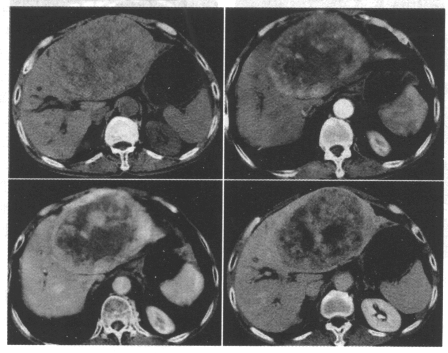

[单选题]患者,男,59岁。肝区疼痛,一月余内体重持续下降,既往有“大三阳”病史。超声提示:肝左叶占位,建议进一步检查。若患者CT检查如下图,首先诊断A.肝局灶

[单选题]男,69岁,肝区疼痛,消瘦乏力三月余,CT检查如图,请作出最可能诊断()A.肝囊肿B.肝脓肿C.肝血管瘤D.肝转移瘤E.巨块型肝癌